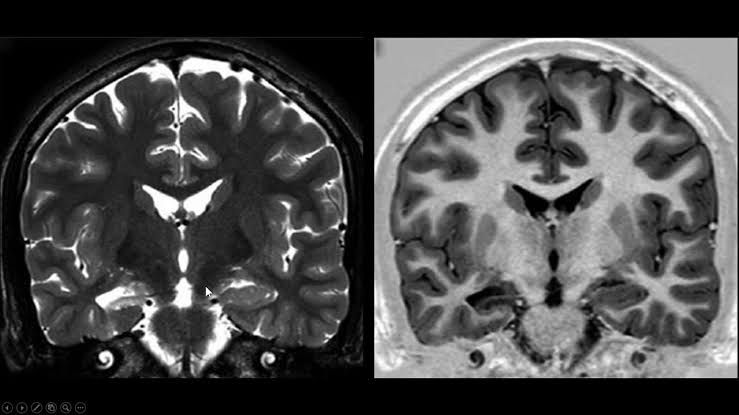

La epilepsia es una enfermedad neurológica crónica caracterizada por crisis convulsivas recurrentes, ocasionadas por descargas eléctricas anormales en el cerebro. Aunque muchos pacientes logran controlar sus crisis con medicamentos, existe un porcentaje importante que no responde adecuadamente al tratamiento farmacológico. A esto se le conoce como epilepsia farmacorresistente, y en [...]